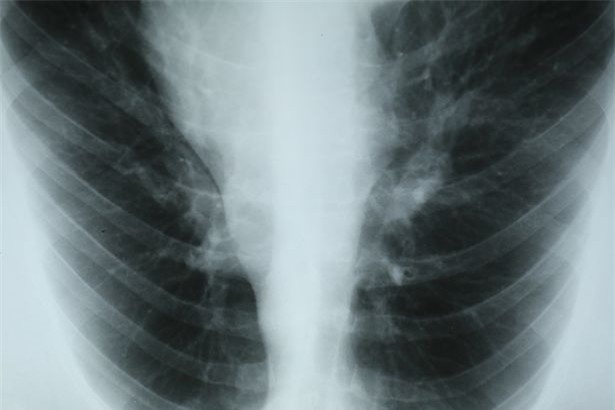

Ban đầu Susan chỉ thấy hơi mệt và khó thở một chút, mặc dù là một người thường xuyên có thói quen tập thể dục. Triệu chứng ngày một trở nặng, Susan đi xét nghiệm và chụp X quang thì được chẩn đoán mắc phải căn bệnh hiểm nghèo không thể chữa được. Căn bệnh u trung biểu mô ác tính có thể giết chết 70% người mắc bệnh chỉ trong vòng 1 năm.